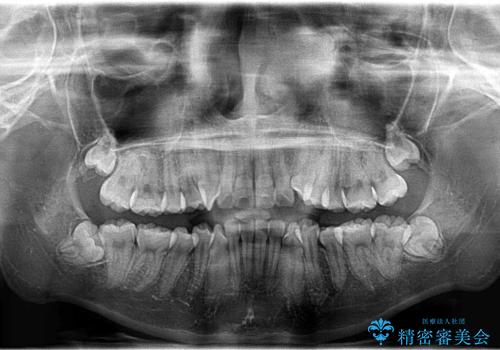

- 上下左右4本の小臼歯を抜歯、ラビアル・ワイヤー矯正を計画した。

抜歯をして第1小臼歯分のスペースを獲得することにより、ガタつきの改善と前歯のリトラクトをおこない、横顔の印象もすっきりとし、整ったEラインを作ることができました。